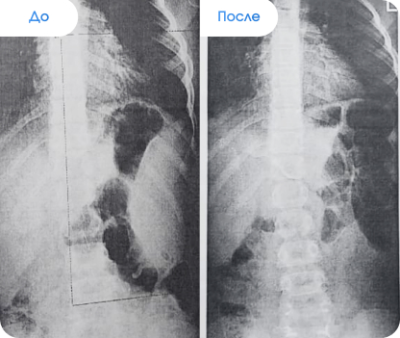

Результаты наших пациентов

✔ После процедуры «Антиспазм подзатылочных мышц» устранен сколиоз III степени, выровнялась выступающая грудная клетка.

✔ После процедуры «Антиспазм подзатылочных мышц» устранен сколиоз II степени, выровнялся таз и длина ног.